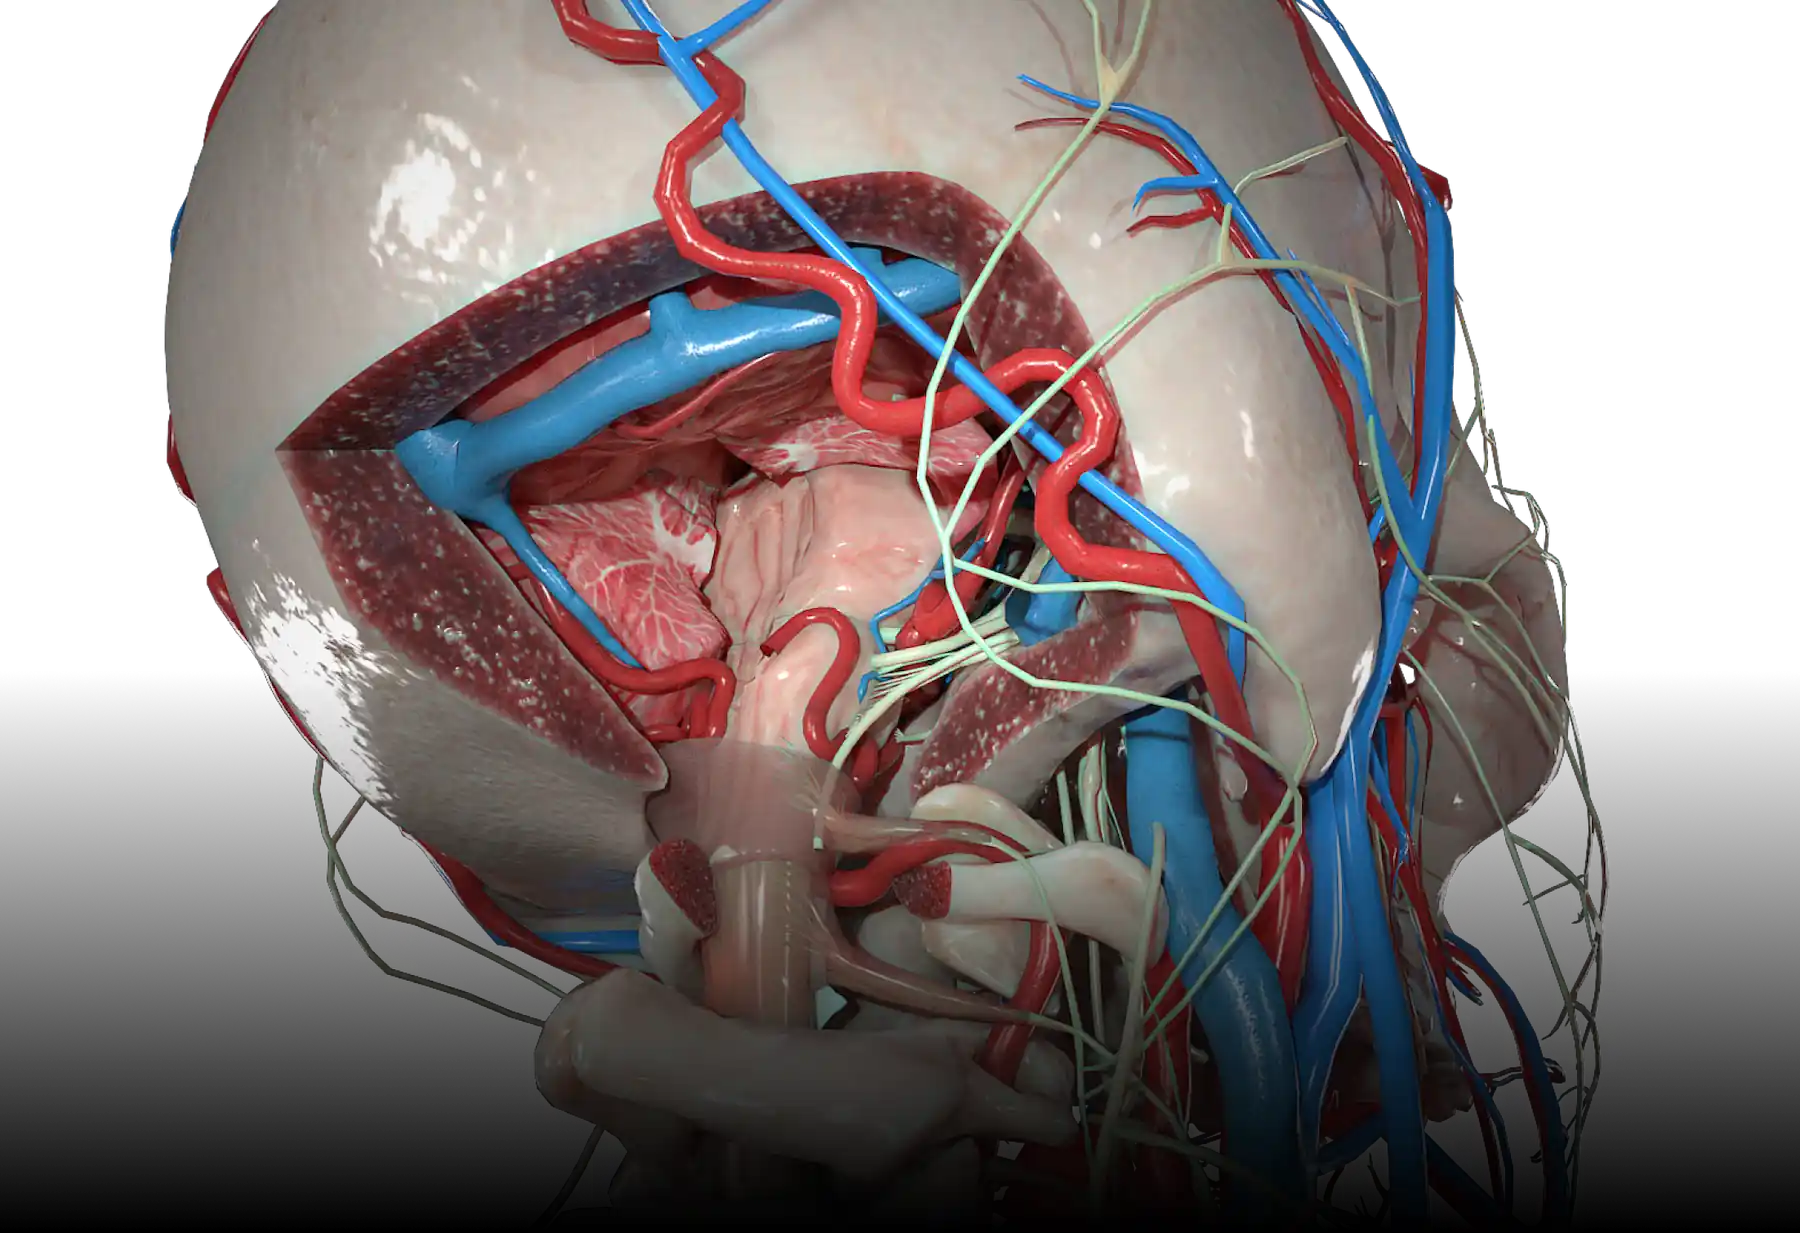

High definition models.

You will get 5,000 meticulously detailed anatomy models, designed to meet rigorous industry standards. Our in-house team has carefully crafted each 3D element, ensuring that you have access to the most accurate and highest quality models available on the market.

High definition models.

You will get 5,000 meticulously detailed anatomy models, designed to meet rigorous industry standards. Our in-house team has carefully crafted each 3D element, ensuring that you have access to the most accurate and highest quality models available on the market.

Full-body 3D learning.

Whether focusing in on the cardiovascular system, skeletal framework, nervous system or more, our immersive 3D experience brings the entire body to life. Perfect for learners at any level.